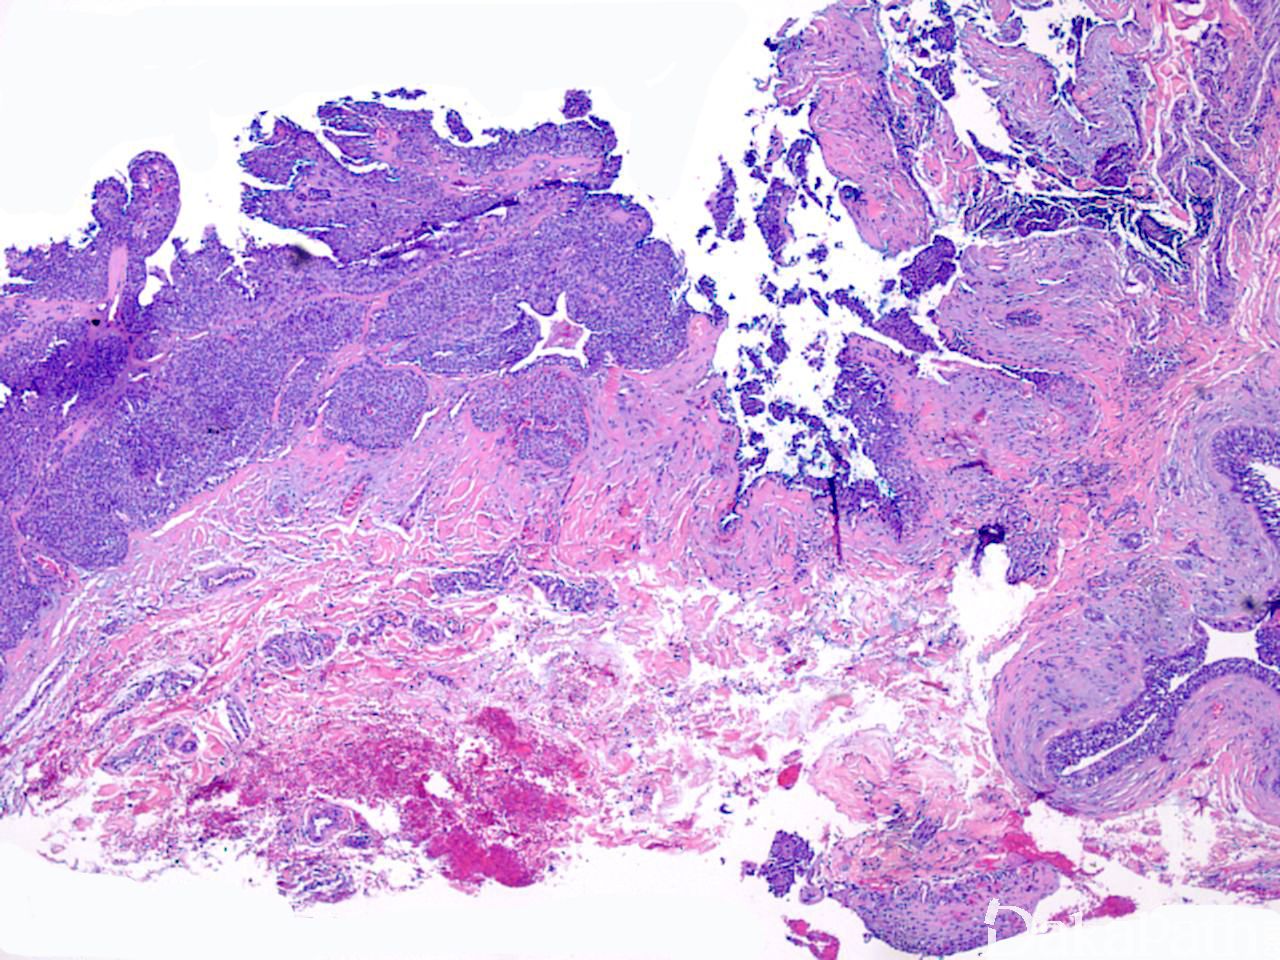

常位于真皮内,较大肿瘤可累及皮下组织,表现为界限清楚的结节,主要为实性,也可为囊实性;

镜下见一致的嗜酸性细胞或糖原丰富透亮大汗腺样细胞增生,形成巢状或小叶状结构;

整个病变均可见到导管结构,一些导管扩张形成囊性区域,囊内充满粉染分泌物;